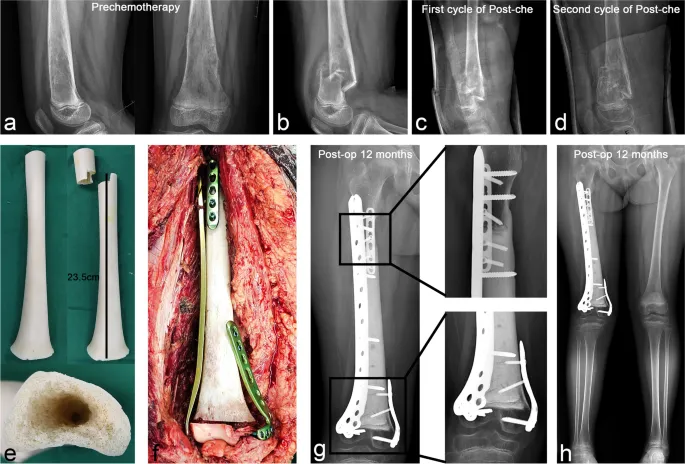

- Filling voids after tumor resection: Allograft struts combined with DBM putty or synthetic bone substitutes.